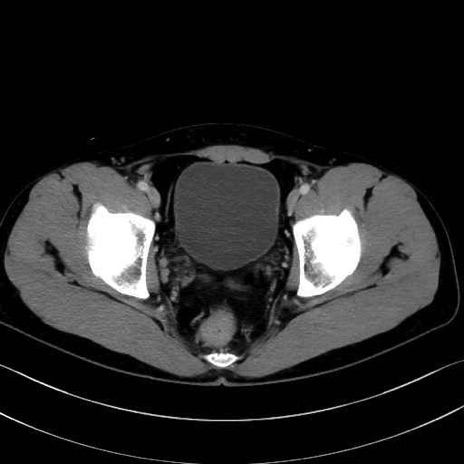

3. 殿部の筋肉(表層・中層・深層)

大殿筋 (Gluteus maximus)

中殿筋 (Gluteus medius)

小殿筋 (Gluteus minimus)

大腿筋膜張筋 (Tensor fasciae latae)